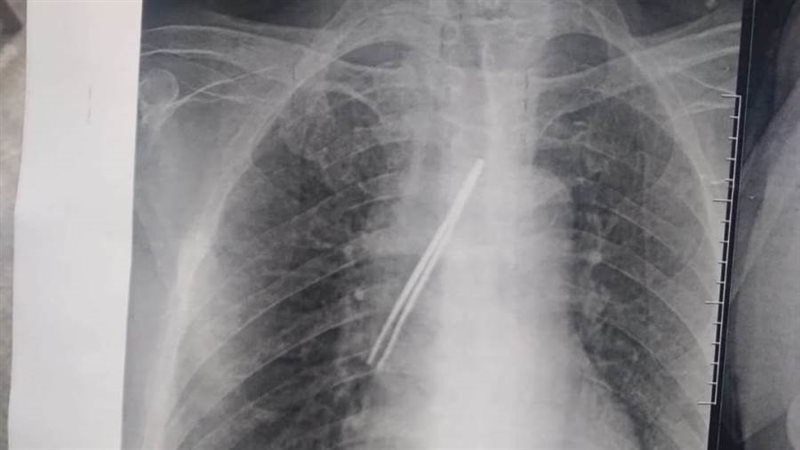

نجح فريق جراحي بقسم جراحة القلب والصدر بمستشفى بنها الجامعي بمحافظة القليوبية، في استخراج "ملقاط شعر"، من القصبة الهوائية لمريض يعاني من شق حنجرى قديم، وأثناء قيامه بتنظيف فتحة الشق الحنجرى بطريقة غير طبية وغير صحيحة باستخدام الملقاط ملفوف بمناديل ورقية، سقط منه وابتلعه ودخل لفتحة القصبة الهوائية.

وأوضح مستشفى بنها الجامعي، في بيان له، أنه تم الآن استخراج "ملقاط شعر" من القصبة الهوائية لمريض يعاني من شق حنجري قديم، وبينما يقوم بتنظيف فتحة الشق الحنجري بطريقة غير طبية وغير صحيحة باستخدام ملقاط ملفوف بمناديل ورقية اتشفط منه الملقاط ودخل لفتحة القصبة الهوائية.

وتابع المستشفى، أنه حضر المريض للقسم في حالة اختناق، وتم دخوله العمليات فورا، حيث نجح الدكتور باسم مفرح الأستاذ المساعد بالقسم، وبمعاونة الدكتور أحمد الخضري مدرس مساعد التخدير، من استخراج "الملقاط"، وخرج المريض بسلامة الله من العمليات ويخضع لاستكمال علاجه بالقسم لحين تماثله الكامل للشفاء.